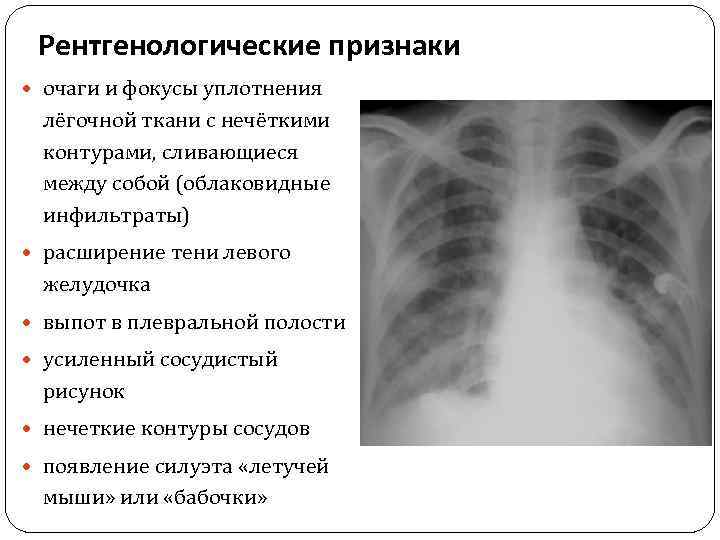

Рентгенологические признаки очаги и фокусы уплотнения лёгочной ткани с нечёткими контурами, сливающиеся между собой (облаковидные инфильтраты) расширение тени левого желудочка выпот в плевральной полости усиленный сосудистый рисунок нечеткие контуры сосудов появление силуэта «летучей мыши» или «бабочки»

Рентгенологические признаки очаги и фокусы уплотнения лёгочной ткани с нечёткими контурами, сливающиеся между собой (облаковидные инфильтраты) расширение тени левого желудочка выпот в плевральной полости усиленный сосудистый рисунок нечеткие контуры сосудов появление силуэта «летучей мыши» или «бабочки»